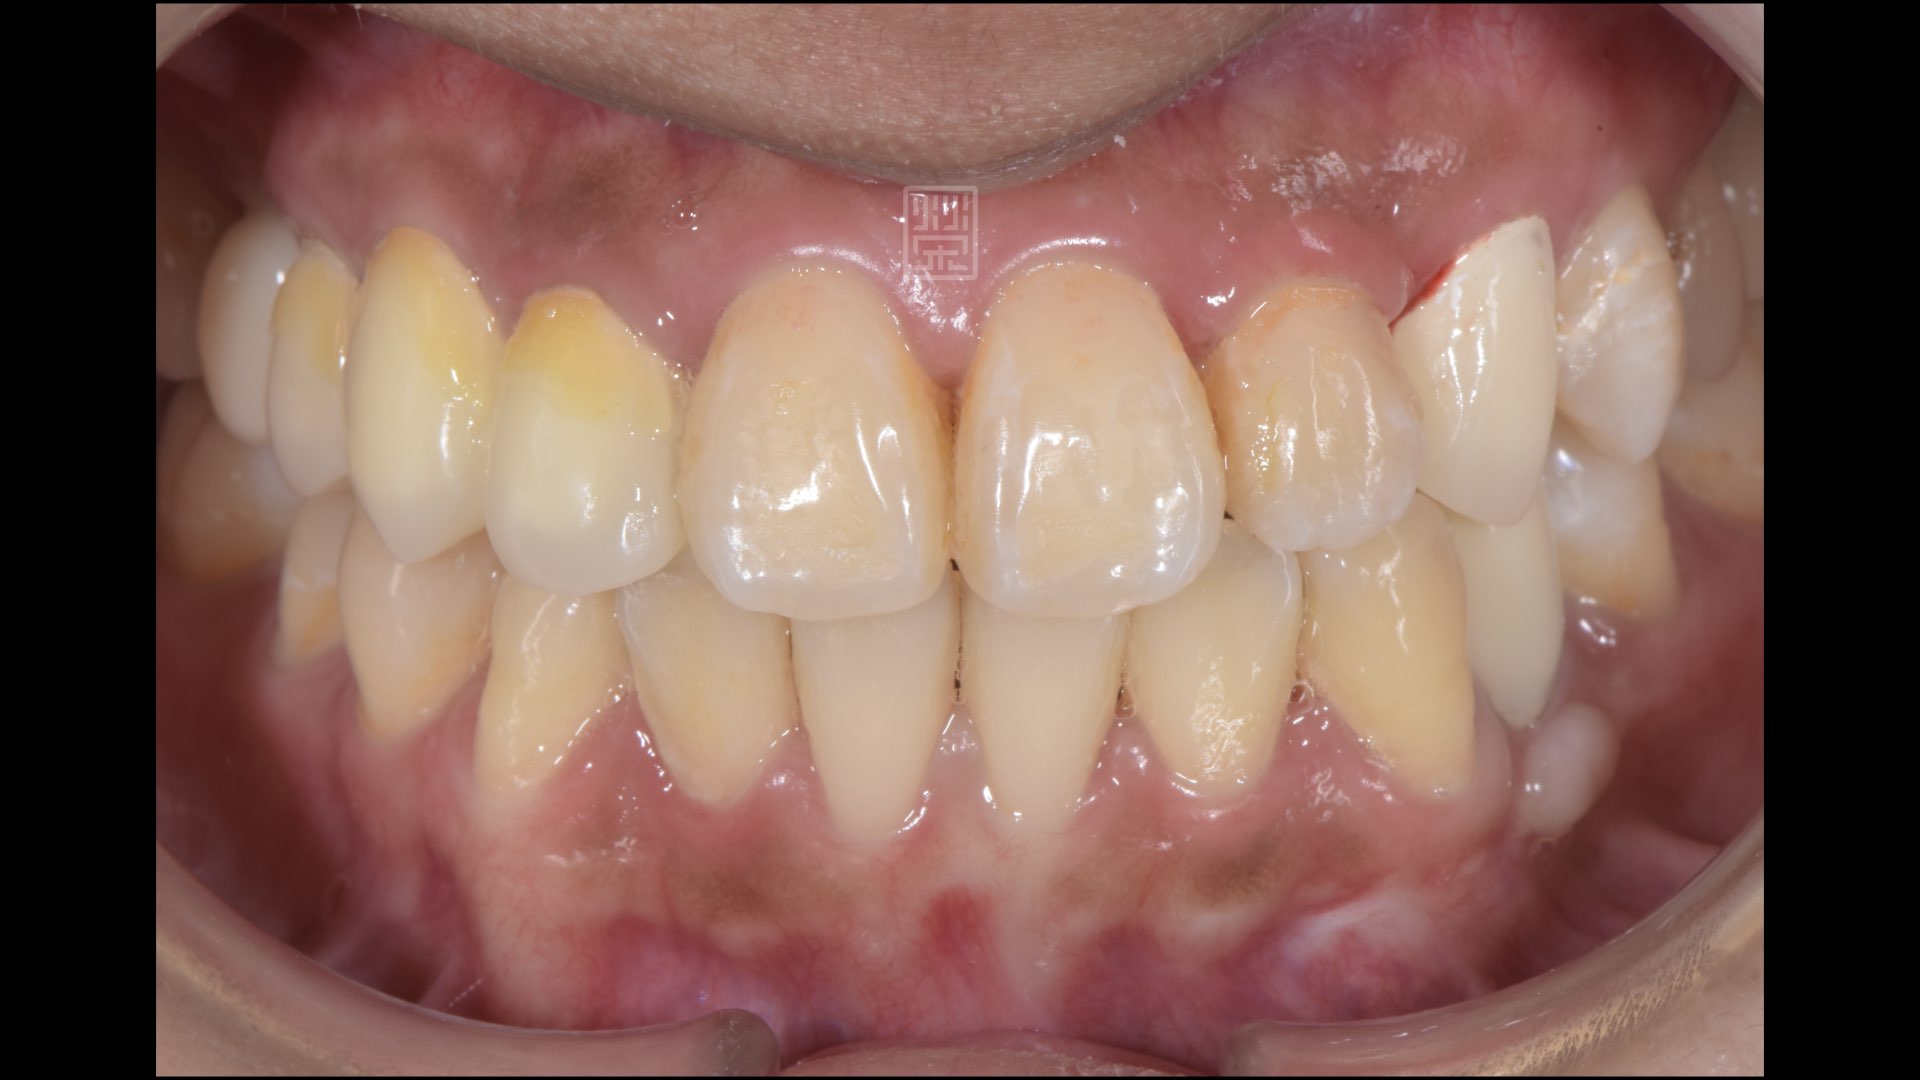

全瓷冠完成,是哪顆呢?

全瓷冠、植牙修復完成